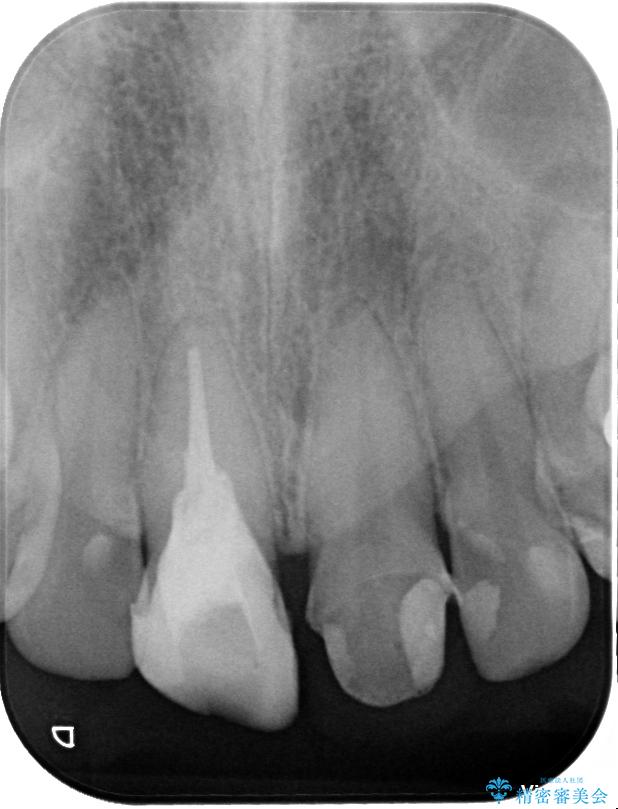

治療前

• 「抜歯してブリッジ」と言われた20代女性が選んだ治療とは|たった4か月で自然な笑顔に抜歯即時インプラント+審美補綴の症例 治療前画像

精密検査の結果、右上中切歯には**フェルール(歯の周囲の健全な歯質)**がほぼ存在せず、このままの状態での保存は困難と判断しました。

■保存治療の選択肢として**挺出(エクストリュージョン)**により歯を引っ張り出し、フェルールを確保する方法も検討可能でしたが、患者様のご希望により、より短期間で審美性を回復できる治療法を選択。